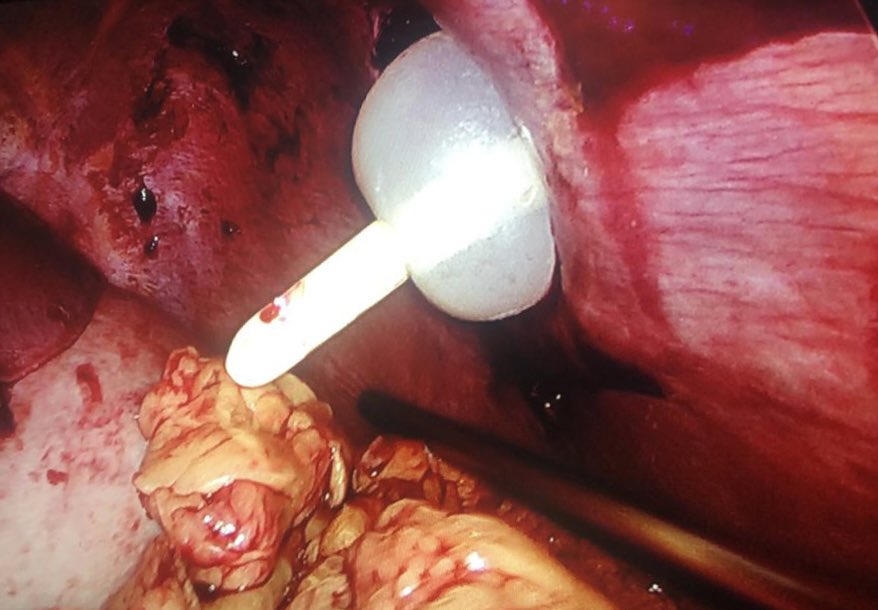

Here we see a patient with an abdominal stab wound undergoing laparoscopic exploration.

A Foley catheter is used to seal the site of the stab wound so that pneumoperitoneum can be maintained.

(photo from @faga7 )